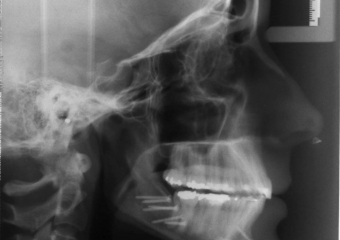

Teleradiografia inicial